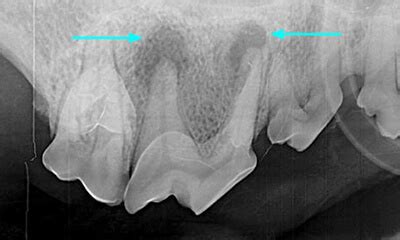

A tooth abscess in dogs is a bacterial infection that occurs in the root of the tooth. It can be caused by a broken tooth, periodontal disease, or other oral infections. The abscess can cause swelling and pain, and if left untreated, can spread to other parts of the body.

The solution to tooth abscesses in dogs is to seek veterinary care immediately. The veterinarian will likely perform a dental exam and possibly take x-rays to determine the extent of the infection. Treatment may include antibiotics, pain medication, and in some cases, extraction of the affected tooth.